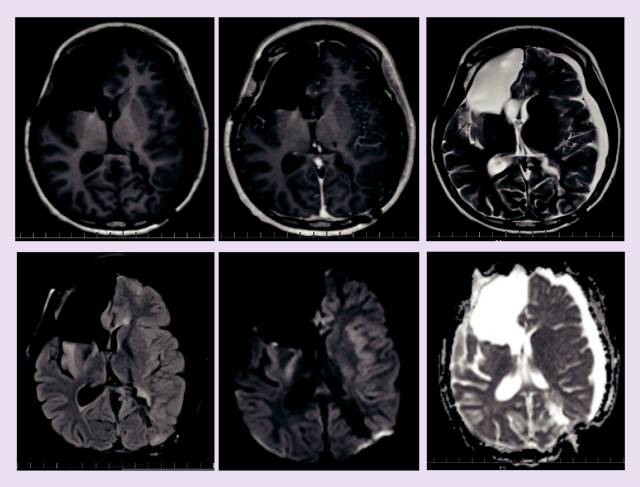

患者在13岁时被诊断为胶质母细胞瘤,在进行手术切除之后,进行了放疗和化疗,但是病情还是进展了。通过MRI 进行了6个月的观察我们可以观察到离散的肿瘤生长,随后,我们开始使用电场疗法进行临床及影像监测7个月,病情稳定。电场疗法起到了预防胶质母细胞瘤复发和抑制其生长的作用,并且在七个月的治疗期间,对13岁的女孩无重大不利影响。我们认为,电场疗法在胶质母细胞瘤的治疗中有潜在价值。

由于她的病史,她需要每个月接受一次评估和神经系统检查,实验室检查和MRI。治疗过程中的副作用非常小,仅为轻微的头皮刺激和皮肤症状,使用非处方药氢化可的松治疗后缓解。她恢复到正常的生活中。在进行电场治疗的6~7个月,病情稳定。7个月后,MRI显示病情进展,患者停止接受电场治疗,继续贝伐单抗的治疗,并做了美国Foundation medicine基因检测公司的全基因组测序。基于检测结果显示ROS1突变,她开始使用克唑替尼治疗。